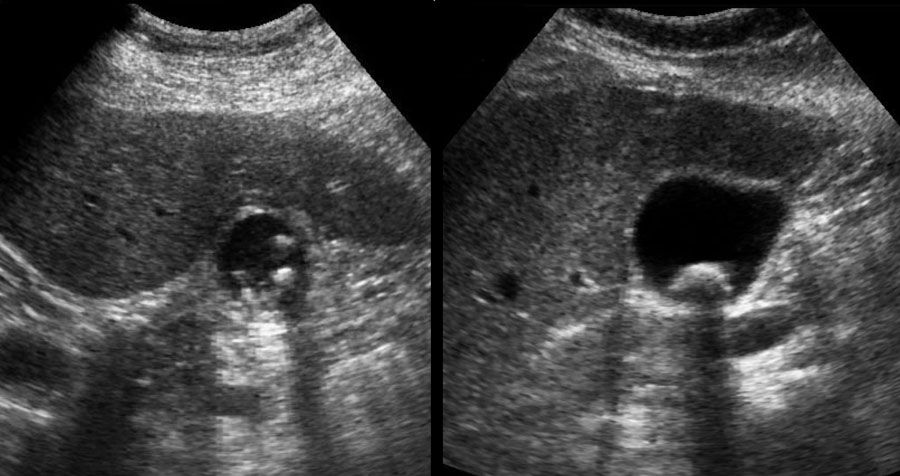

Dưới đây là hai ví dụ về sỏi kẹt được phát hiện trong cơn đau quặn mật ở các bệnh nhân khác nhau.

Ở tư thế nằm ngửa, một viên sỏi (mũi tên) được phát hiện tại cổ túi mật.

Sau khi đứng dậy, cúi người và đi lại, viên sỏi (mũi tên) không di chuyển xuống, do đó phải là sỏi kẹt.